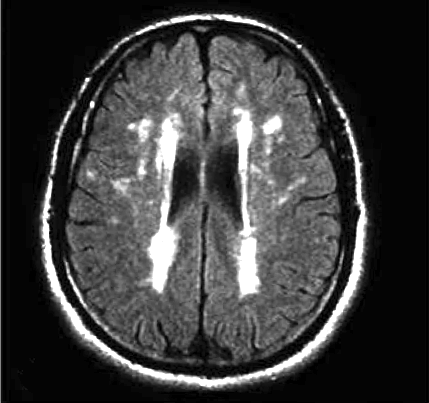

La progressió de la leucoaraiosi tendeix a seguir un patró general. Inicialment s’observen les lesions periventriculars a la zona del marge (barrets) dels ventricles laterals (Fig. 1) estenent-se, en relació amb la severitat del fenomen, al voltant d’ells (Fig. 2).

L’escala qualitativa de Fazekas (Fig. 3) és la més utilitzada per determinar la magnitud de les lesions de la substància blanca en IRM, classificant:

– Grau 0: absència de lesió;

– Grau 1: existència de lesions focals;

– Grau 2: inici de la confluència de lesions;

– Grau 3: lesions difuses que comprenen regions senceres.